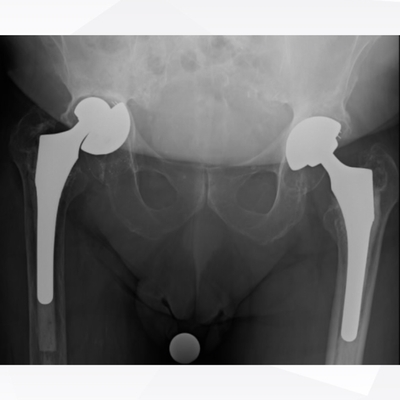

Click on an image below to view more info.